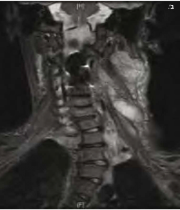

| 06:16, 3 באוגוסט 2014 | נוירוגנית3.png (קובץ) |  |

114 קילו־בייטים | Motyk | 1 | |